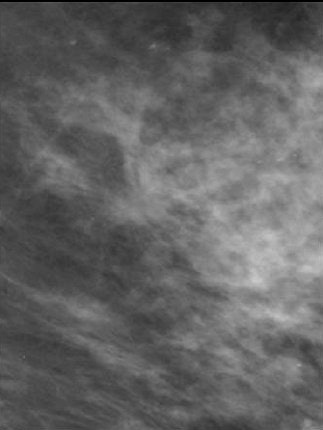

![]() |

| Above, conventional mammogram on which cancer is obscured. Below, DBT slice on which cancer is clearly defined. Images courtesy of Richard Moore and Dr. Daniel Kopans. |